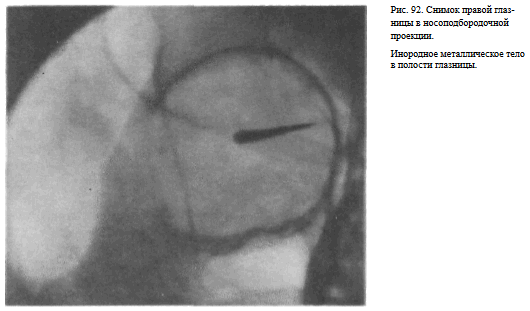

В этой же укладке может быть выполнен снимок одной (правой или левой) глазницы. В таких случаях центр снимаемой глазницы соответствует центру кассеты, и на него отвесно направляют пучок излучения, используя тубус или диафрагмирование пучка излучения с помощью щелевой диафрагмы. Фокусное расстояние—100 см (рис. 88).

На прицельном снимке каждой из глазниц в этой же проекции, как правило, небольшие изменения структуры стенок, а также мелкие инородные тела глаза видны лучше. Такие снимки широко используют в офтальмологической практике (рис. 92).